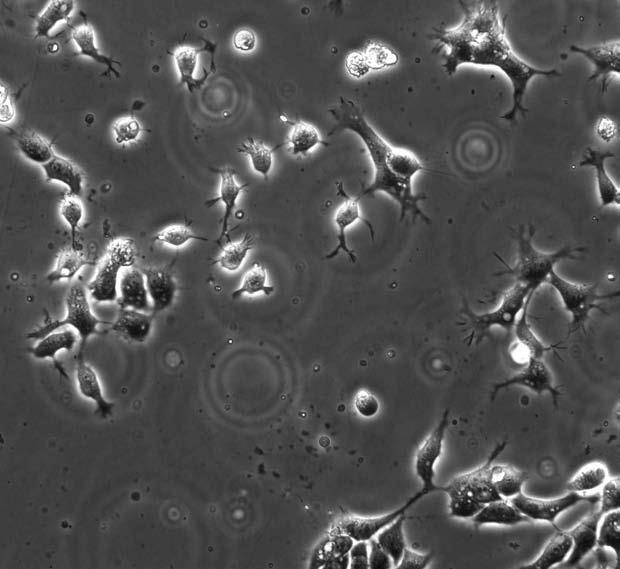

Эмбриональные стволовые клетки человека под микроскопом

Помните о клоне наиболее пластичных стволовых клеток, умеющих превращаться в любую ткань? Их называют эмбриональными стволовыми клетками, потому что они образуются в процессе эмбрионального развития и откладываются в организме «про запас». Эти клетки получают в наши дни методом терапевтического клонирования. Суть его сводится к тому, что у человека в любом возрасте берут самую обычную клетку и пересаживают ее ядро в донорскую яйцеклетку, которая немедленно начинает дробиться – прямо в пробирке. Через пять дней она достигает стадии бластоцисты – полого шарика из нескольких сотен клеток, значительная часть которых приходится на универсальные стволовые. Такие клетки можно размножать и неограниченно долго поддерживать в виде клеточной культуры, а их полная генетическая идентичность тканям пациента исключает проблемы с иммунитетом.

Но в клинической медицине их используют крайне редко – только по жизненным показаниям, когда никакое другое лечение уже не помогает. Беда в том, что они способны превратиться во что угодно, очень плохо понимают химические команды взрослого организма и склонны к неограниченному делению. Если их ввести в организм, они легко могут спровоцировать злокачественный рост или вызвать образование тератом[51], что и было не раз показано в экспериментах на животных. Например, крысам, страдающим искусственно вызванной болезнью Паркинсона[52], пересадили эмбриональные стволовые клетки и добились массового их превращения в нейроны. Сначала все шло хорошо, и состояние крыс заметно улучшилось вплоть до полного исчезновения симптомов болезни. Однако на 10-й неделе эксперимента дифференцировку[53] сохранили всего 25 % нейронов, остальные же вновь превратились в неспециализированные клетки, которые начали активно размножаться, заселяя крысиный мозг. Руководитель опытов Стивен Голдман так прокомментировал наблюдаемую картину: «Не нужно быть нейроонкологом, чтобы понять, что этот процесс – начало образования опухоли».